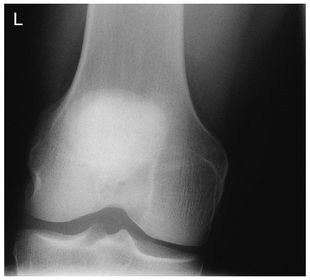

AP Bilateral Weight Bearing Knees 40 SID 14x17IR in wall BUCKY MANUAL TECHNIQUE for bilateral PHOTOTIME for unilateral - CR perpendicular to IR @ 1/2 in below apex of patella for average sized pts - CR angled 5-10 degrees cephalic for hypersthenic pts